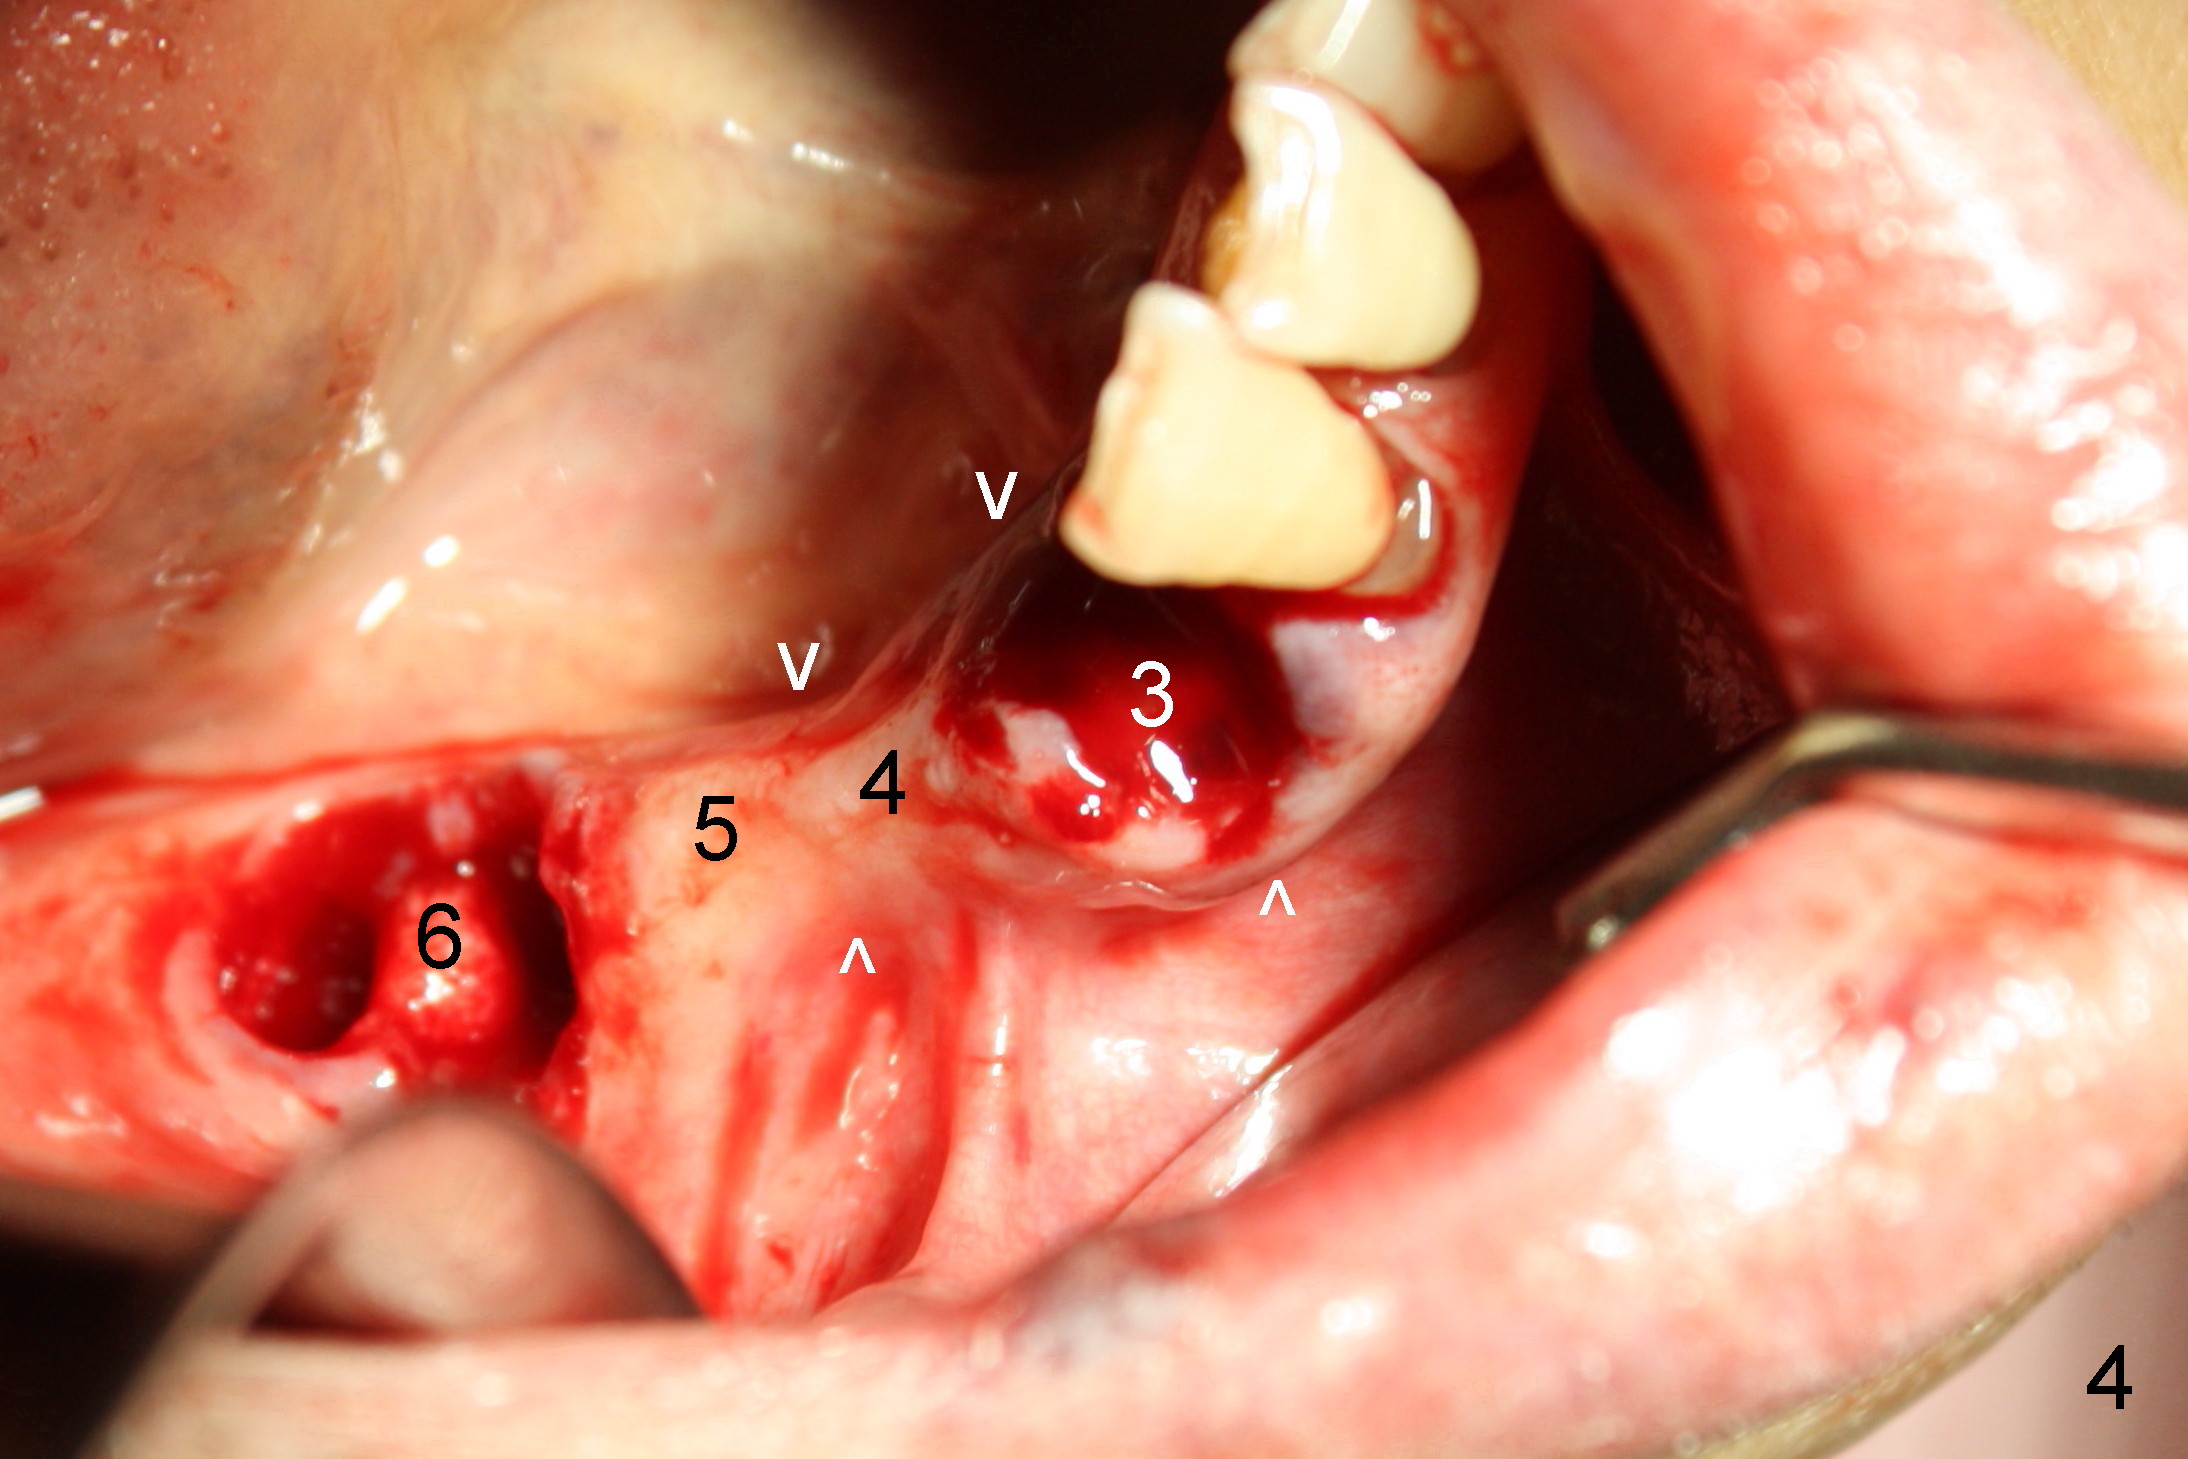

The lower right bridge (from canine (Fig.2: 3) to 1st molar (Fig.1: 6)) fails while a 77-year-old man is undergoing chemotherapy for urinary bladder cancer. The abutments of the bridge are extracted without plan for implants (Fig.4). Four months later, the patient returns for implants (Fig.3), but the ridge is narrow (Fig.5). While 2 of 3x14 mm 1-piece implant are placed at the canine and 1st bicuspid sites, 2 piece ones at the 2nd bicuspid and 1st molar sites (Fig.6: 3.5x11 mm, 5x14 mm). Soft (Fig.7-10) and hard (Fig.11) tissues heal 1 week (Fig.7) and 4 months (Fig.8-11). There is minimal bone resorption 1 year 7 months post cementation (Fig.12,13, non-splinting). It appears that narrow diameter implants are a valid solution to narrow ridge at the sites of the lower canine and premolar. As long as there are enough implants for function, the crowns are not necessary to be splinted. Surprisingly, the patient starts flossing after implant restoration. Retrospectively an immediate provisional bridge should have been fabricated.